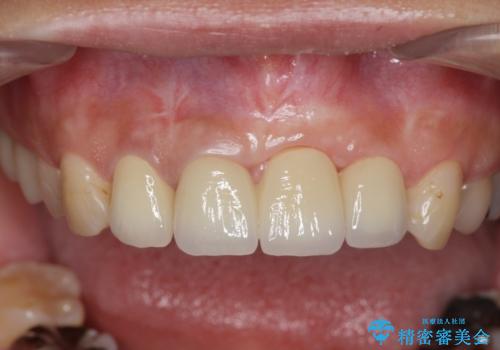

- 前歯の見栄えの悪さの改善を求めて来院されました。

左側の前歯には他院で埋入されたポジションの悪いインプラント補綴により歯冠長の長いクラウンが装着されており、感染による排膿も認められこのまま審美性を改善するのは難しい状態です。

不良インプラントを除去し最終的にブリッジによる補綴で審美性の改善を行うこと、その準備として骨の造成・歯肉の移植による歯の欠損部顎堤のボリュームを維持・増大を計画します。